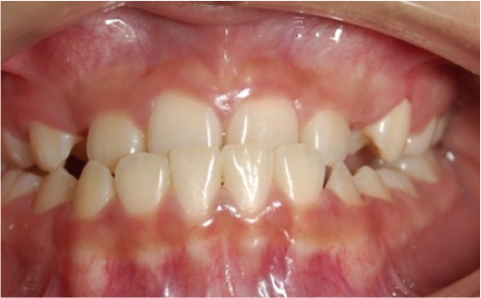

Tratamiento ortopedico para descruzar mordida

Después